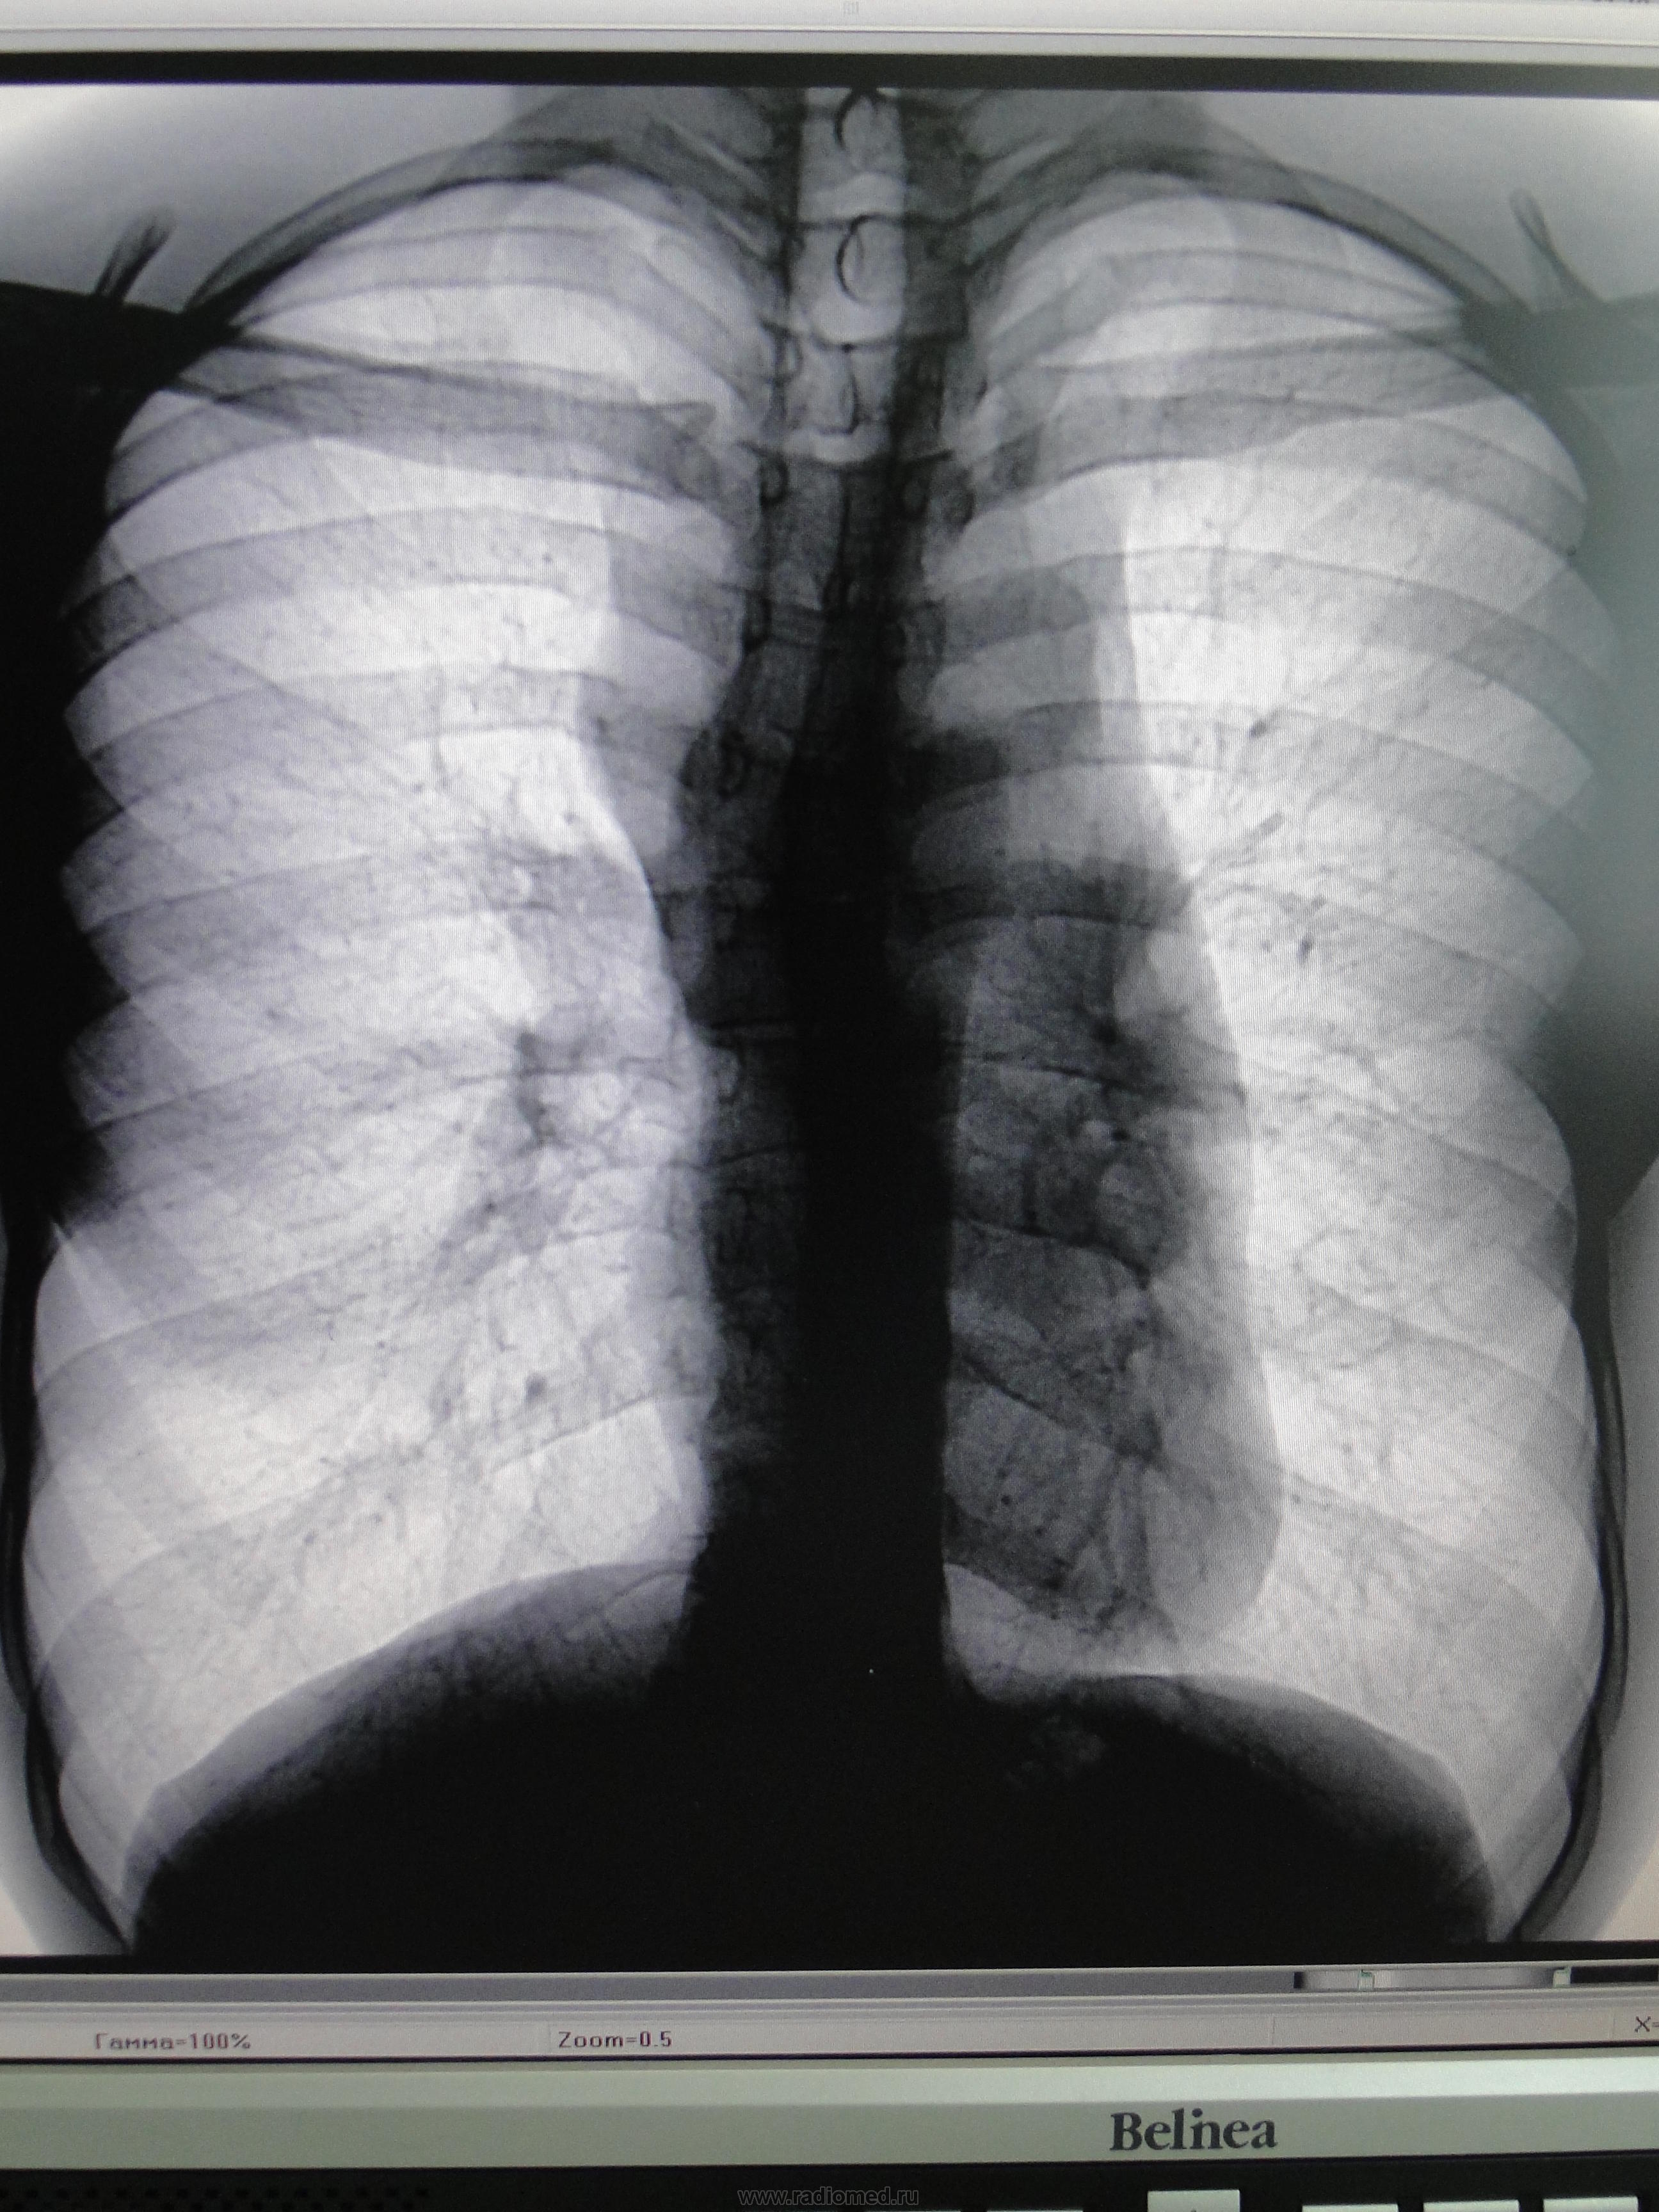

Парень, 22г, сегодня проходил профосмотр, вызван на дообследование.В архиве за 2004-05 описано "сглаживание талии cor", снимков не видела.Думаю о врожденной СС патологии.Что это может быть?

КТ - если есть возможность. И обязательно с контрастированием, т.к. помимо "паруса" в верхнем средостении мне кажутся и "шары". Не верится, что чистая тимома...

по снимку-я бы сказала что там лимфоузлы, тем более что описание ранее "сглажена талия" никак не вяжется с тем. что сейчас. чтобы вообще можно было вести речь о врожденной патологии

Больше похоже на загрудинное образование, тимому или зоб. Боковой нужен. Линейная томография через корни и срединные боковые +\- 2-4 см в стороны.

Здравствуйте.Верхнее средостение расширено,двумя руками за не редуцированную вилочковую железу

+1 - Тимома.

лимфогранулематоз или тимома

Какой интереснй боталлов проток. Картинка совсем для открытого протка не типичная, скорее атипичная, не характерная

Видите ли Кат, речь не о том, есть или нет открытый боталлов проток. А о том, что патогенез гемодинамических нарушений при открытом боталловом протоке, никак не объясняет расширение, структуру, характер контуров тени верхнего средостенья. Не согласны? тогда поясните, какие анатомические структуры ее образуют?

Вчера явился этот молодой человек.Из разговора: первые изменения на Rg были выявлены в 2007г при прохождении комиссии в военкомат,но все заканчивалось кардиологом.Примерно с того же времени беспокоят покалывания в груди.Принес только последние снимки (хотя просила результаты всех проведенных ранее исследований-от кардиолога и рентгенолога), боковой не качественный -с разворотом и жесткий,хотя постфактум можно рассмотреть.Сделала Tg: в передне-верхнем средостении образование 10*12 см с четким контуром,однородной структуры. Отправила на КТ -попросила вернуться с результатами и по возможности предыдущие пренести-обещал.Уверена,что вернется; результаты,естественно,выложу.